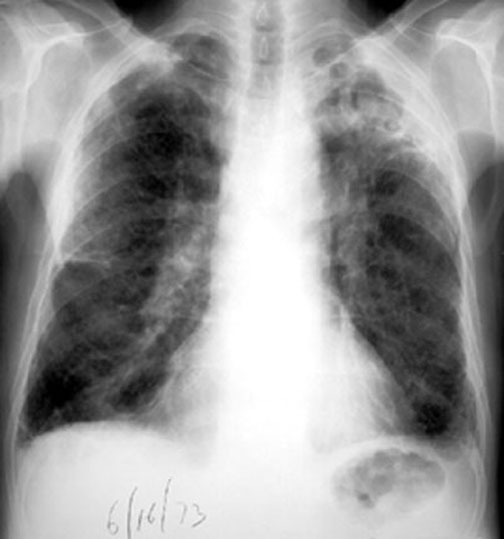

Case 4

Lateral

Labeled Image

What are the contents of a cavity?